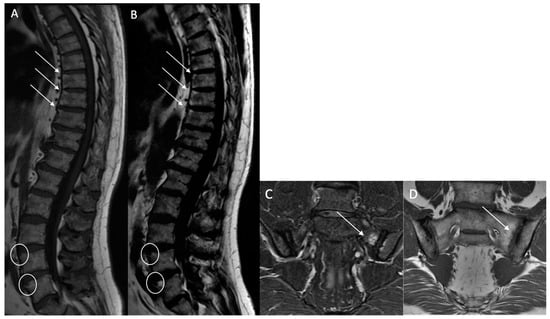

Ankylosis (A): Defined as bony ankylosis with heterotopic bone formation and no discal space on both sequences (Figure 5).

Figure 5. Lumbar vertebral ankylosis with “squared vertebrae” in a 54-year-old patient. A T1w sagittal sequence showing vertebral ankylosis with corporeal vertebral partial bone fusion from T9 to T11 and from T12 to L2 (arrows). The “squared” aspect of the corporeal vertebrae is noted (A). A T2w Dixon (fat) image better showing vertebral ankylosis with corporeal vertebral partial bone fusion (arrows) (B).